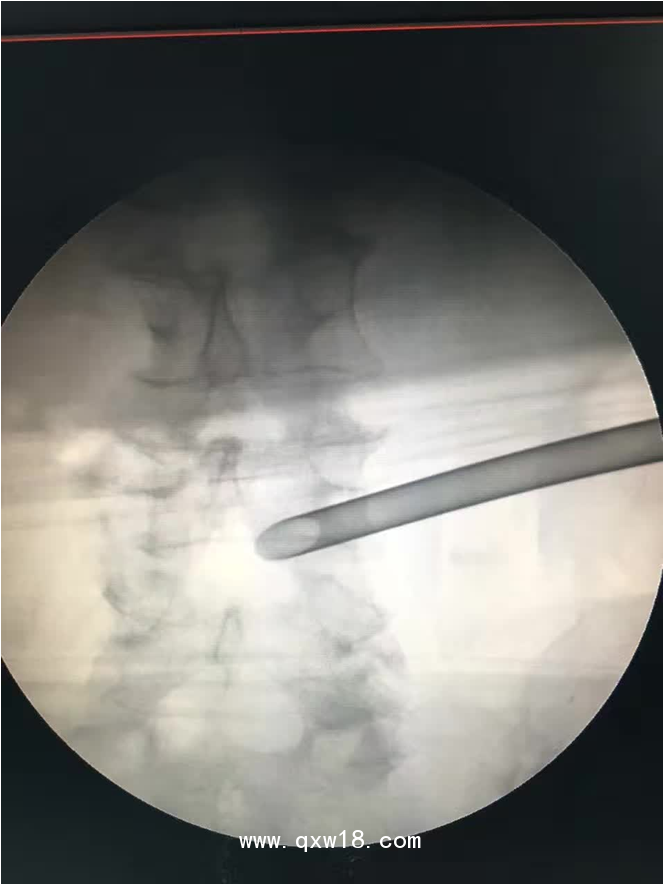

椎間孔鏡品牌椎間孔鏡椎間孔鏡技術(shù)椎間孔鏡培訓(xùn)產(chǎn)品說(shuō)明:

portant; word-wrap: break-word !important;">椎間孔鏡手術(shù)圍手術(shù)期注意事項(xiàng):